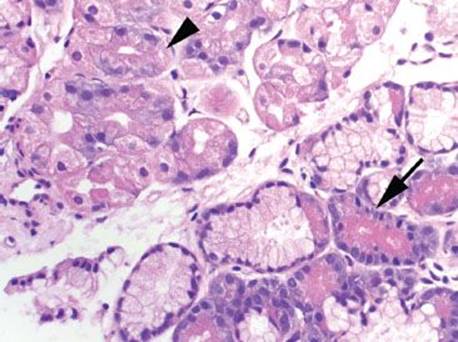

Figure 2.110 Chronic gastritis pattern, pancreatic metaplasia/heterotopia. Pancreatic differentiation (arrowhead) is seen as a lobule of pancreatic acinar cells and is etiologically nonspecific. The background in this example is unremarkable oxyntic mucosa. In normal stomachs, this finding is probably heterotopic rather than metaplastic whereas in stomachs with autoimmune gastritis, pancreatic type tissue is probably metaplasic.

Figure 2.111 Chronic gastritis pattern, pancreatic metaplasia. Higher magnification of previous case (Fig. 2.110). This focus shows pancreatic acinar cells (arrow) which are wider at the base than at the luminal apex. Brightly eosinophilic, coarse zymogen granules fill the cytoplasm and the cells have basally located small, uniform nuclei. By comparison, parietal cells (arrowhead) are polygonal with finely granular eosinophilic cytoplasm. The nuclei may be centrally or basally located, and are larger by comparison. A trypsin stain may be useful in difficult cases (pancreatic cells would display trypsin reactivity and oxyntic cells would be trypsin nonreactive).

Figure 2.112 Chronic gastritis pattern, pancreatic metaplasia, AMAG. Lobules of pancreatic metaplasia (arrowheads) are present in this gastric body biopsy of a patient with AMAG. Intestinal metaplasia and total atrophy of oxyntic glands are present in a background of a chronic inflammatory infiltrate. Based on the presence of damaged background mucosa, this pancreatic tissue is best regarded as metaplastic.

Figure 2.113 Chronic gastritis pattern, pancreatic metaplasia, AMAG. Higher magnification of previous case (Fig. 2.112). The pancreatic acinar cell (arrow) is seen in the same field as Paneth cells (arrowhead) in the background of complete intestinal metaplasia. By comparison, the Paneth cells have coarser and more brightly eosinophilic zymogen granules.

Pyloric metaplasia is the replacement of the oxyntic mucosa with pyloric glands. Although this finding is highly characteristic of AMAG, it is not always a dominant pattern of injury. More often, adjoining intestinal metaplasia (IM) is far more prominent, particularly at low power. With IM, the cells of the surface and pit epithelium change such that they morphologically and histochemically resemble the small or large bowel, a finding that can be categorized as complete (type I) or incomplete (type II). Complete IM resembles normal small bowel epithelium with fully developed goblet cells, enterocytes with a brush border, and Paneth cells. In advanced cases, the contour of the mucosa develops villiform architecture and crypts. In contrast, incomplete IM (type II) has a mixture of goblet cells and normal gastric epithelium, and it lacks a brush border, Paneth cells, and absorptive cells. IM (complete or incomplete) may be seen in both AMAG and EMAG. Finally, the less common pancreatic acinar metaplasia is found in over 20% of AMAG cases and is frequently seen in conjunction with pyloric or intestinal metaplasia. These nested or lobulated collections of pancreatic acinar cells stain with amylase (75%).